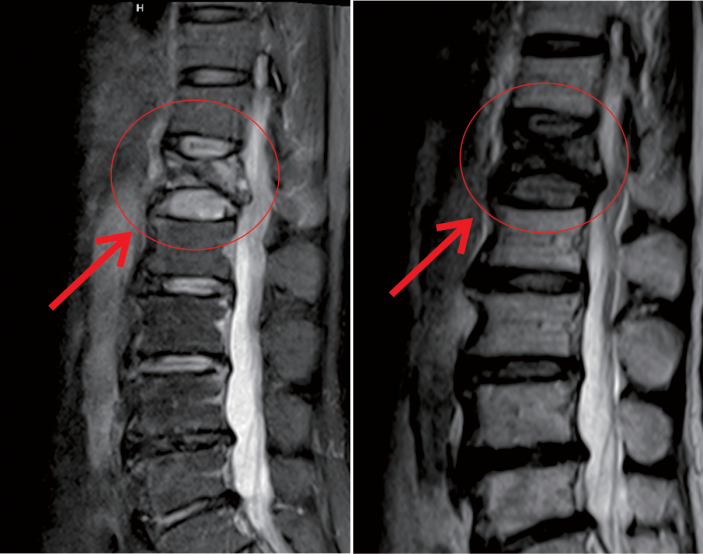

在我院先進的術中三維CT引導下,杜教授确定L1雙側椎弓根進針點,娴熟地将穿刺針穿入L1椎體,經穿刺針建立通道将約11ml骨水泥注入坍塌的椎體中。術中監視,注入的骨水泥逐漸支撐起原本壓縮空洞的椎體。骨水泥凝固後,病變的椎體迅速恢複了承重能力。手術持續約40分鍾,開展非常成功,術後老人的疼痛馬上消失,翻身也無疼痛,第二天就能使用助步器下地行走。

△術前MR顯示,第一腰椎壓縮性骨折

△術後,病變的椎體迅速恢複了功能